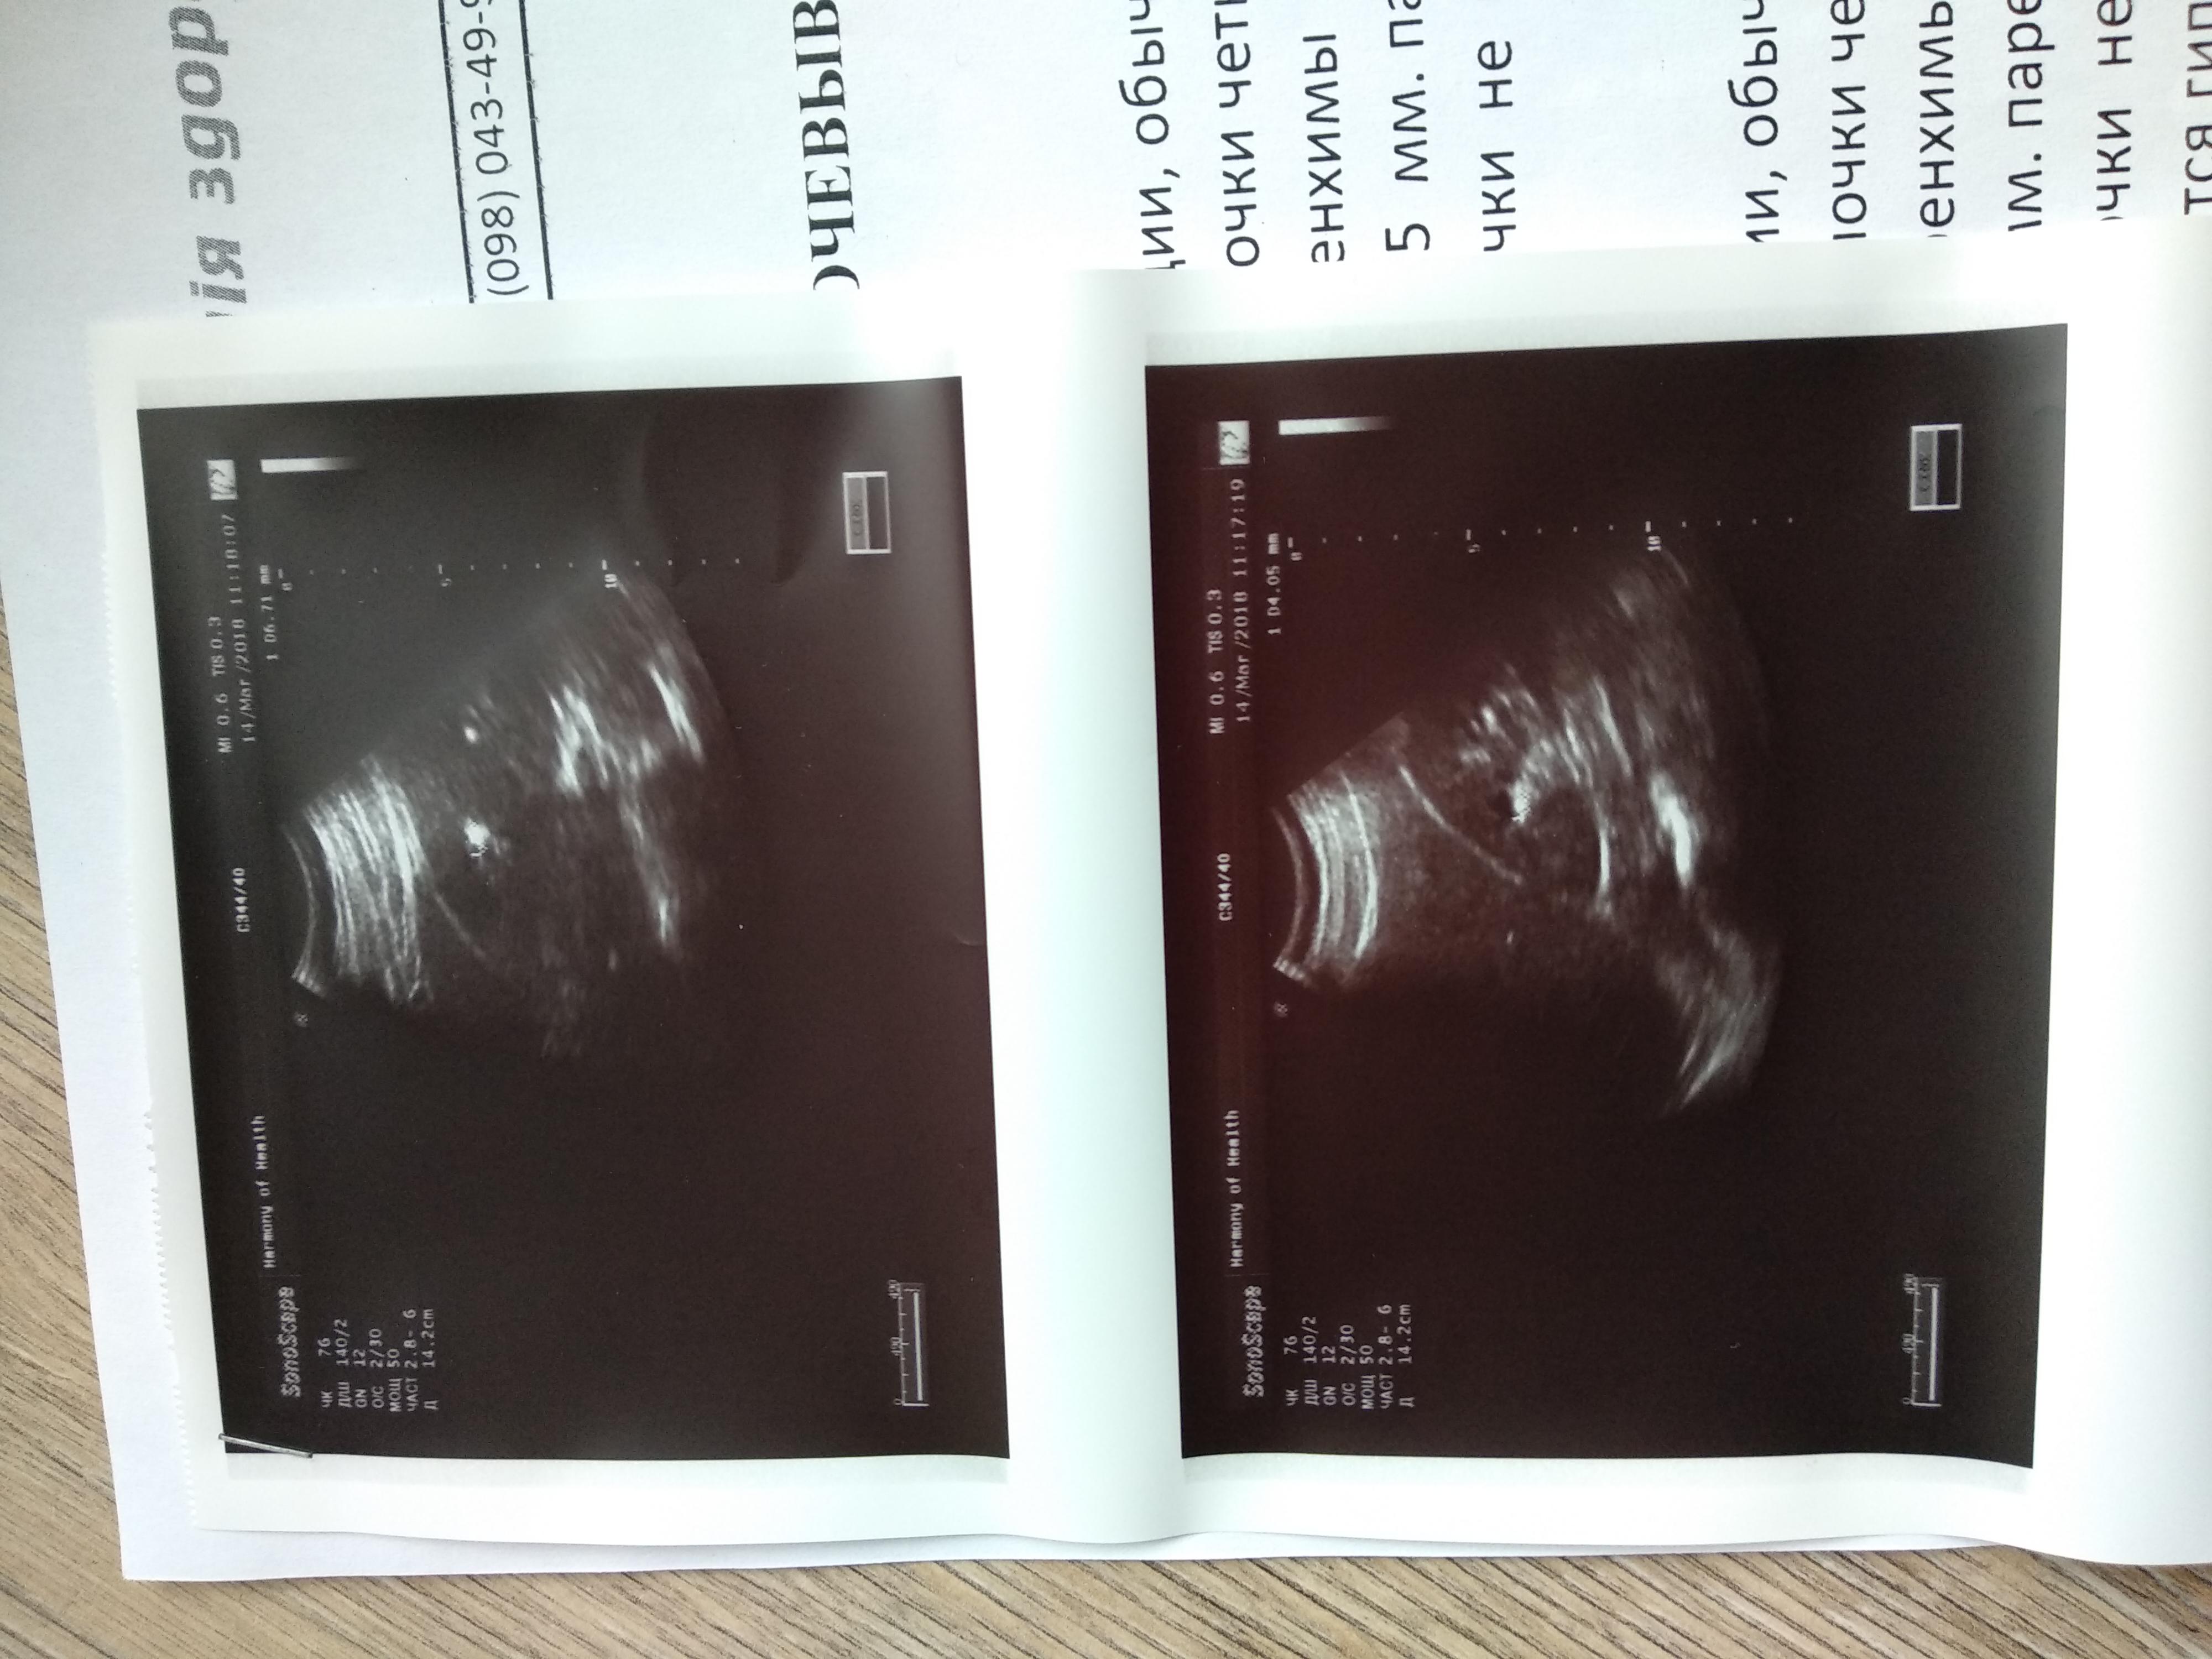

Мучают боли в почках, год назад сделали операцию пиелолитемию слева.